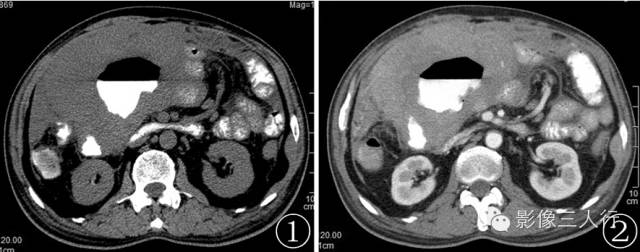

图 2 , 3 CT 增强 :肿块呈明显不均匀强化 ,周围见肿大淋巴结